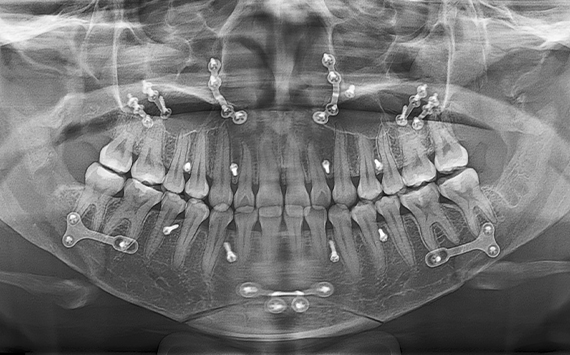

3D CT와 안면 스캔 등

고성능 진단 장비로 턱뼈 구조와

교합 상태를 정밀하게 분석합니다.

정확한 진단은 치료 방향과

결과의 완성도를 높이는 첫걸음입니다.

서울페이스21은 고성능 3D 진단 시스템과 3D 모의 수술 프로그램을 활용하여,

수술 전 정밀한 분석부터 수술 과정, 그리고 수술 후 예상되는 얼굴형 변화까지 체계적으로 시뮬레이션합니다.

이를 통해 환자 개개인의 골격 구조와 특성을 반영한 맞춤형 수술 계획을 수립하여 보다 정교한 수술을 제공합니다.